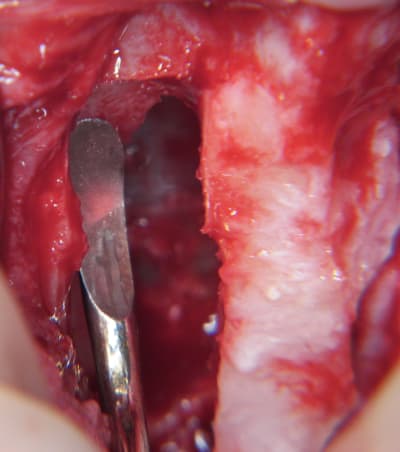

- forage et transperçage de la crête sans aller trop loin...

- essayage pilier pour parallélisme

- forage à 3mm

- visualisation de la hauteur sous la membrane de Schneider

- utilisation d'un ostéotome diamètre 3.4 puis 3.8

(sous dimensionnement de diamètre par rapport à l'implant prévu :4mm)